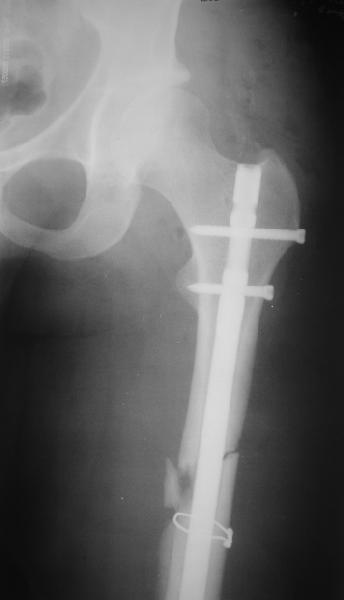

фото несращения бедра